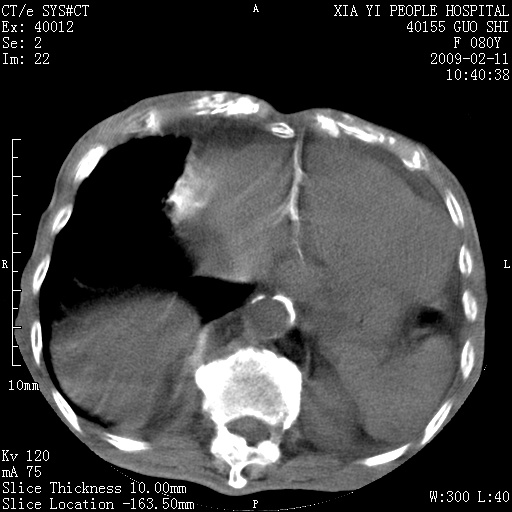

以下是引用随光逐影在2009-2-16 16:34:00的发言:[br]1)考虑右前纵隔皮样囊肿。2)双侧少量胸腔积液。

以下是引用zjzjr在2009-2-16 17:30:00的发言:[br]支持囊性畸胎瘤 双侧少量胸腔积液。